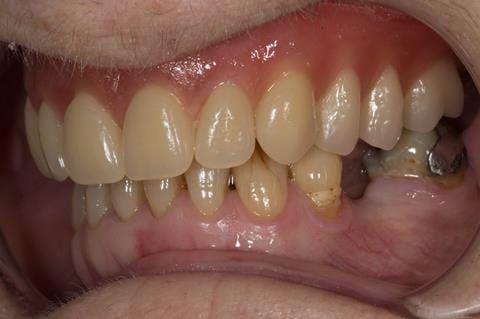

- Poorly fitting cobalt chromium based maxillary partial denture, which has been added to. This exhibited poor retention, stability and tissue fit (support). Unable to wear a new acrylic based denture.

- UR7 - occlusal amalgam. 10- 20% alveolar bone loss. Healthy periodontium with reduced attachment level. No mobility.

- Eight mandibular anterior teeth worn incisal edges from now extracted maxillary anterior crowns. Gingivitis - owing to inadequate oral hygiene.

- LL6 with large amalgam restoration - healthy periodontium.

- Bruxism.